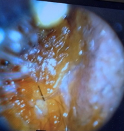

1. Take a look at the Impacted Wax with Video Otoscopy

4. A Clear Ear Canal Post Irrigation